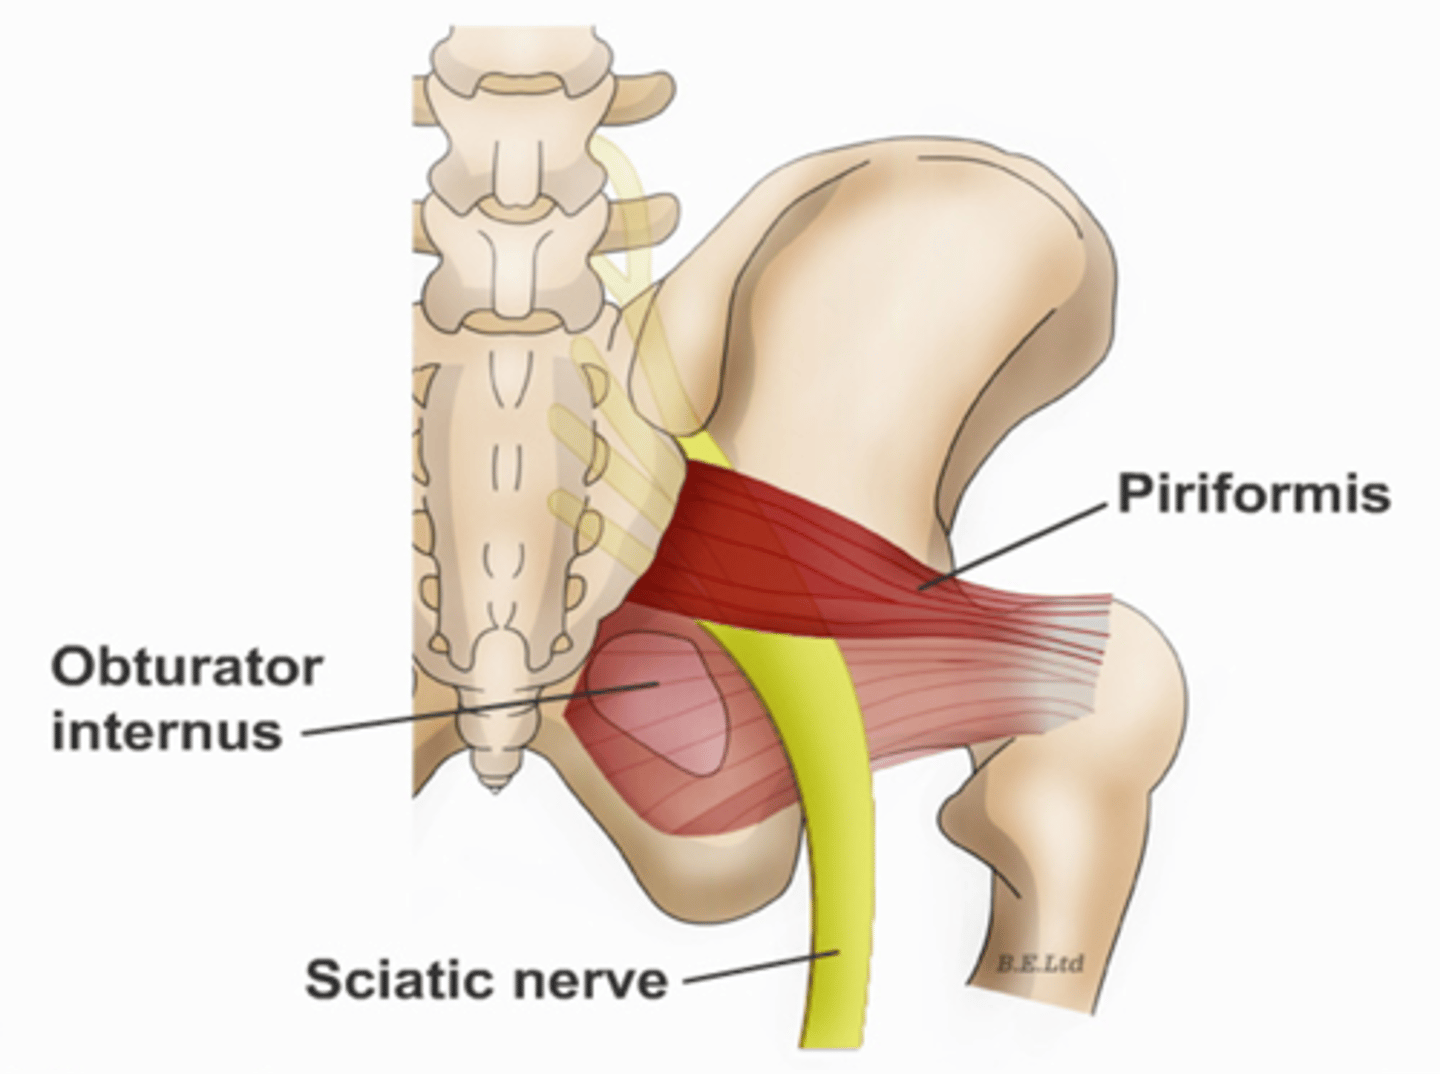

Obturator internus muscles line the ___ walls of the true pelvis

lateral

Piriformis muscles are in the ___ region of the true pelvis behind the ___

posterior; uterus

What muscle is often mistaken for ovaries?

piriformis